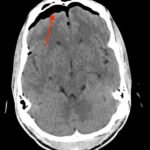

Tension pneumocephalus is a rare neurosurgical emergency requiring cranial decompression to prevent permanent neurological injury, herniation, and death. In this report, we present a trauma patient struck by a knife in the forehead who presented with agitation and vomiting. Imaging ultimately revealed a minimally displaced frontal sinus fracture through both the anterior and posterior walls of the sinus. This disruption, acting as a ball-valve for air entry into the cranium, resulted in extensive pneumocephalus and eventual tension physiology. The patient required immediate neurosurgical decompression. This case illustrates both the importance in recognition of this uncommon pathology as well as the need for rapid reassessment with clinical changes in trauma patients.